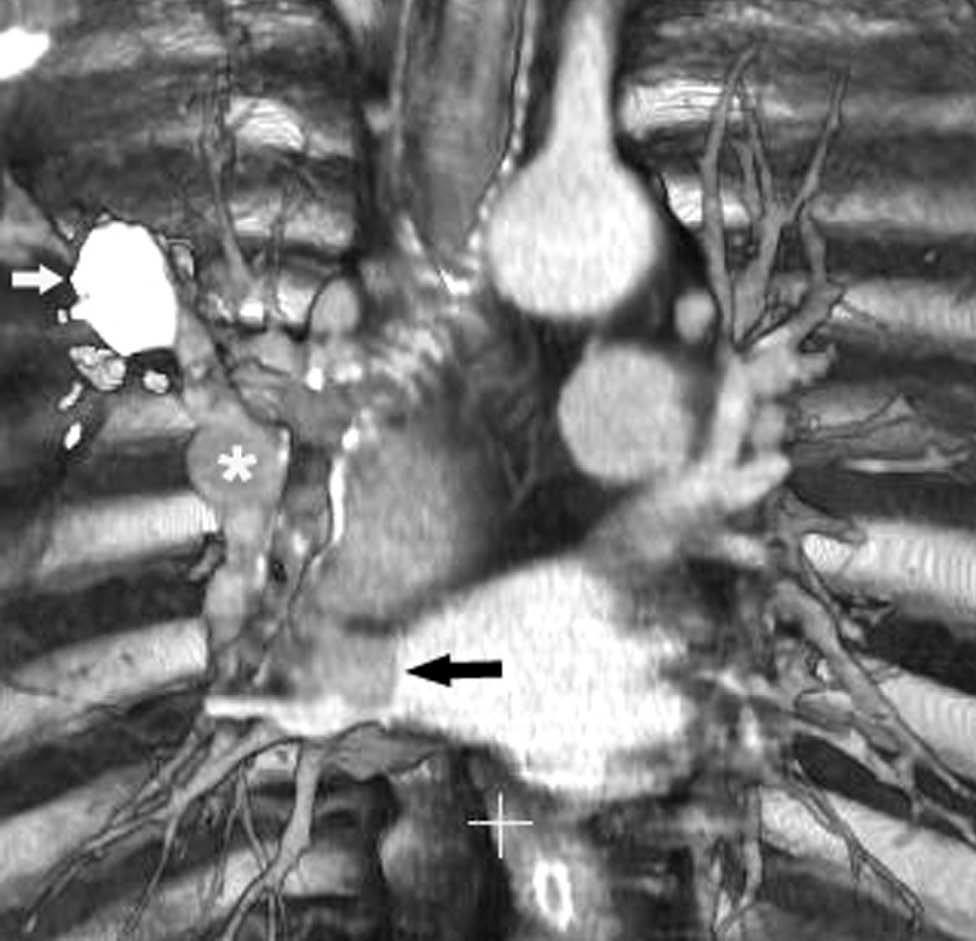

Fig. 11.--N2. (A) Corte axial de tomografía computarizada (TC) con contraste. Nódulo heterogéneo en el segmento 6 del lóbulo inferior derecho con infiltración de la vena pulmonar inferior (flecha). (B) En la reconstrucción de volumen se ponen de manifiesto la infiltración tumoral de la vena pulmonar (flecha negra), la adenopatía hiliar (asterisco) y una adenopatía calcificada lobar superior derecha (flecha blanca).

La precisión de la TC para predecir la afectación ganglionar mediastínica, pese a la ayuda que suponen las reconstrucciones MPR y 3D en la valoración de determinados territorios ganglionares (espacio subcarinal, hilio o ventana aortopulmonar) (fig. 11), sigue teniendo muchas limitaciones. El único criterio que se emplea para considerar que un ganglio es patológico es el tamaño (cuando el eje corto es mayor de 10 mm, salvo en el espacio subcarinal que se acepta hasta 12 mm). El empleo únicamente de criterios de tamaño hace que la TC sea una técnica poco precisa en la valoración de la afectación ganglionar. En un metaanálisis reciente13 la sensibilidad global de la TC para estadificar el mediastino fue de un 57%, con una especificidad del 82%, un valor predictivo positivo (VPP) del 56% y un valor predictivo negativo (VPN) del 83%. Lo que es innegable es la capacidad de la TC para mostrar un mapa de los ganglios tanto hiliares como mediastínicos (fig. 12), lo cual es de gran utilidad en la determinación del factor N. La valoración del territorio hiliar puede ser compleja por la agrupación de estructuras vasculares, por lo que además de la opacificación adecuada de éstas, es de utilidad la identificación de la pérdida del ángulo de la bifurcación (carina secundaria), ya que el eje corto significativo en este territorio es de 3 mm. Como ya hemos comentado, también es de gran ayuda en esta localización el empleo de reconstrucciones (fig. 11)5.